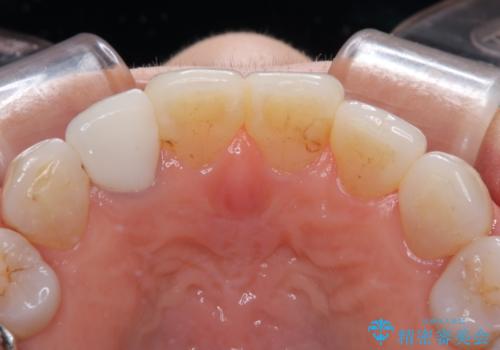

- 奥歯の目立つ銀歯と、神経が失活して変色した前歯を気にして来院された患者様です。

銀歯と歯の間に隙間があり、冷たいものがしみる知覚過敏の症状が認められたため、銀歯を白くするだけでなく、知覚過敏症状の改善も狙って補綴治療を行うこととしました。

長年口を開ける度に気になっていた銀歯が一気に自然な色合いとなり、患者様には大変満足していただけました。